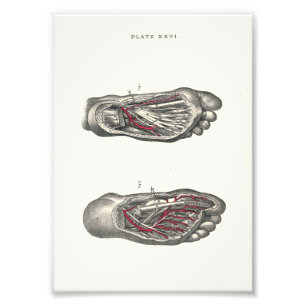

Poster d'anatomie interne Pied & Ankle

Prix32.95 CHF